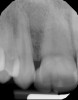

Fig 9 and Fig 10. An implant placed in site No. 10.

Figure 9

When the patient was 18 years old, an implant was placed in site No. 10 with no complications (Figure 9 and Figure 10). Three months later, a periapical radiograph was taken, the implant was torque tested, and a healing abutment (3 mm by 4 mm by 4 mm) was placed.